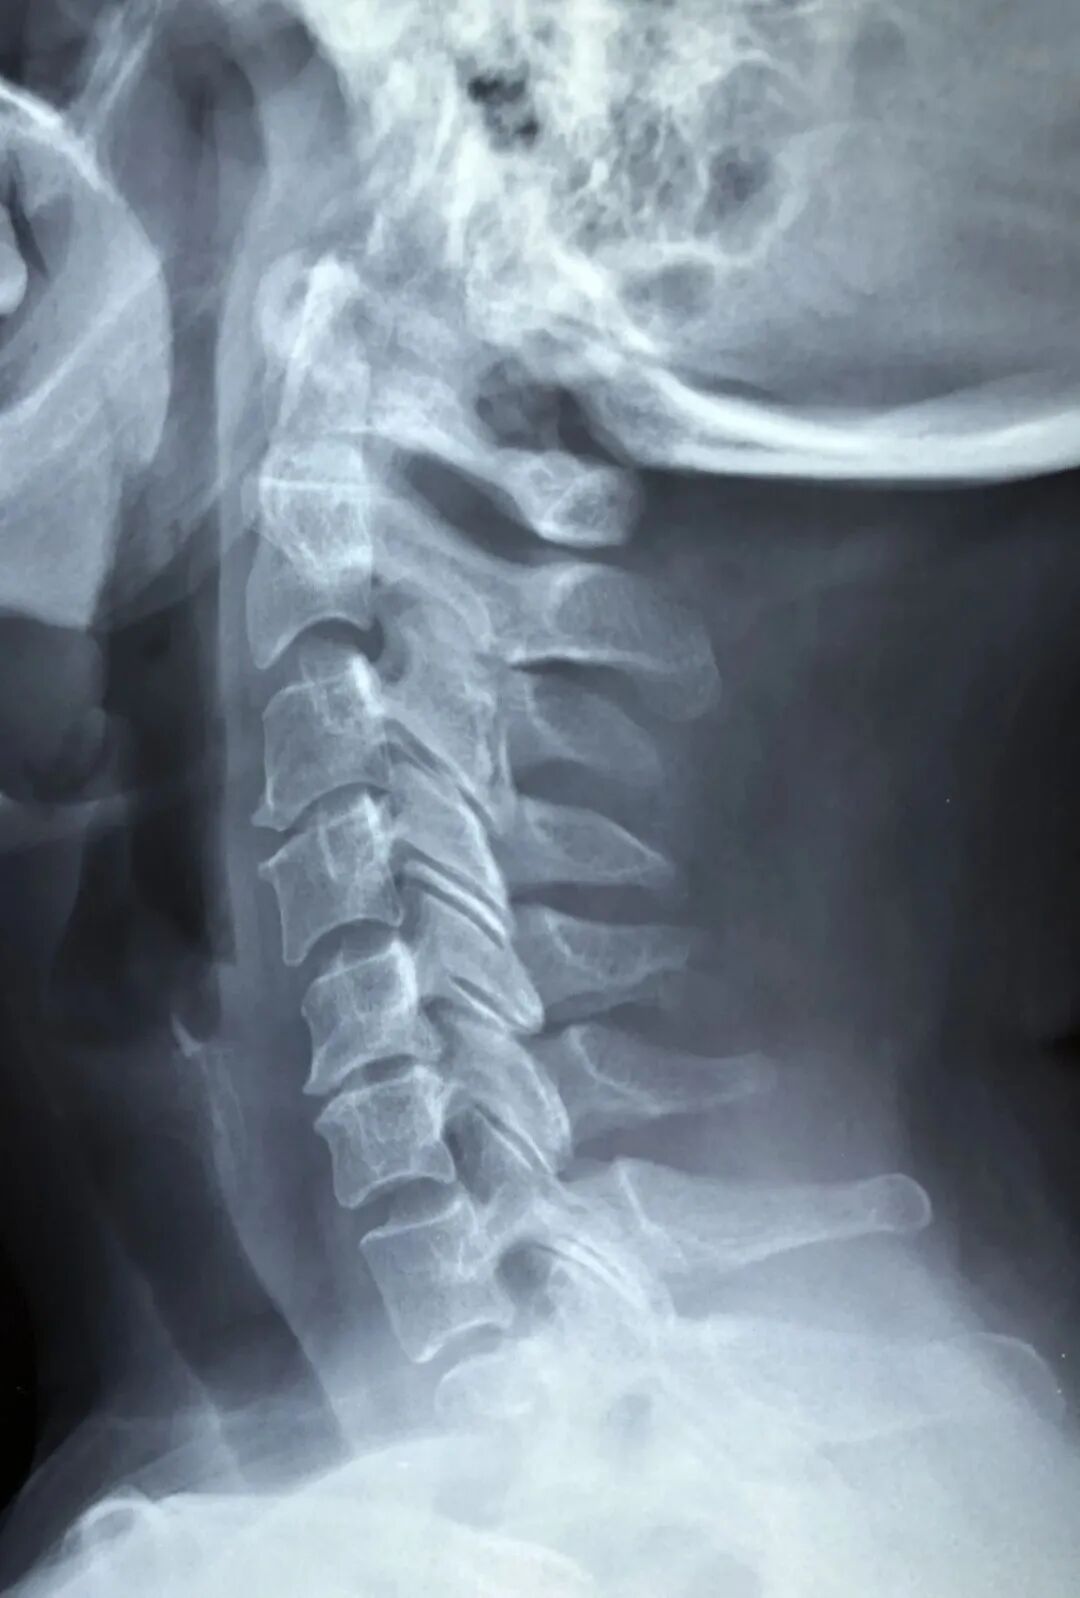

最常用CT、核磁急性中风、脊柱外伤先做CT,详细分析时可用核磁

脑和脊髓

最常用核磁,其次是CT

脊柱(颈椎、腰椎、胸椎)